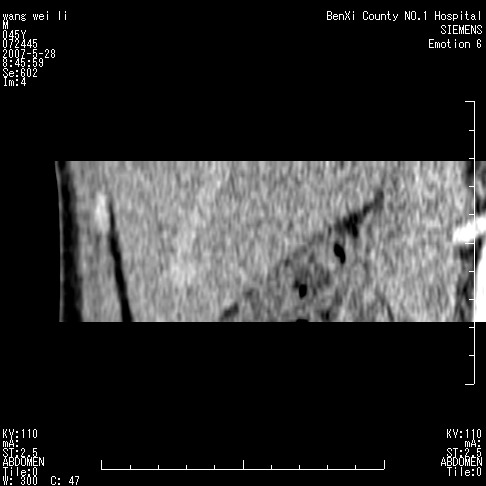

以下是引用还珠格格在2007-5-28 12:06:00的发言:[br]肝右叶后段病灶动脉期结节状强化,既然静脉期、延迟期为等密度充填 应考虑 肝右叶后段典型血管瘤。